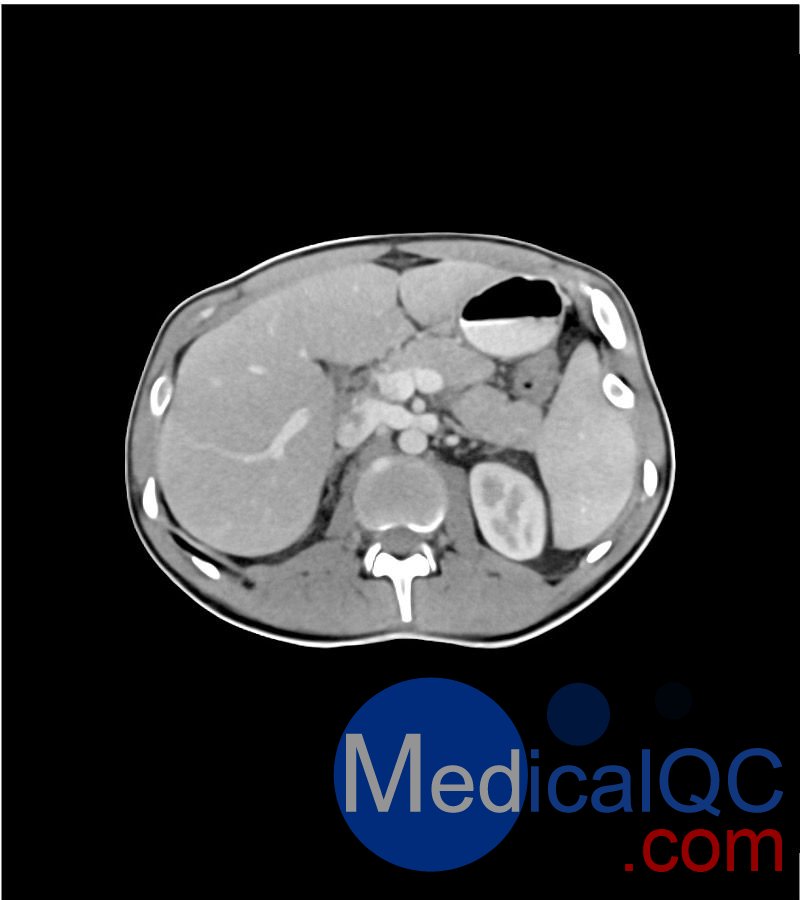

WEK-5501男性腹部模体,WEK-5501男性骨盘模体成像效果图:

WEK-5501男性腹部模体,WEK-5501男性骨盘模体

WEK-5501男性腹部模体,WEK-5501男性骨盘模体可模拟门静脉期的腹部和盆腔增强扫描效果,扫描范围覆盖第一腰椎至会阴区域。

该体模右侧设有髂淋巴结肿块(模拟病灶)。

1. 可对脉管系统、骨骼及软组织进行逼真模拟,涵盖的器官包括肝脏、胆囊、胰腺、脾脏、肾上腺、肾脏、胃、小肠、结肠、膀胱及前列腺。

2. 右侧设有髂外淋巴结肿块(模拟病灶)。